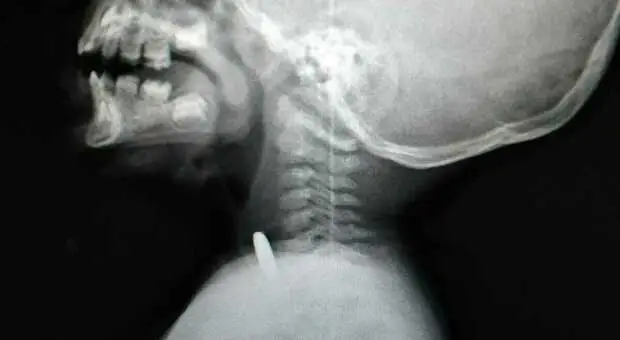

Napoli, bimbo di 2 anni ingerisce pila a disco: operato d?urgenza al Santobono

Bimbo di due anni Ingerisce pila a disco: operato d?urgenza al Santobono. Ricoverato in terapia intensiva in prognosi riservata ma non in pericolo di vita. Il piccolo aveva ingerito una una di...